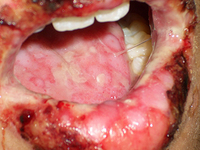

Um paciente do sexo masculino de 17 anos diagnosticado com síndrome de Stevens-Johnson induzida por azitromicina. Erosões e crostas nos lábios com úlceras difusas na língua

Ferrandiz-Pulido C, Garcia-Patos V. A review of causes of Stevens-Johnson syndrome and toxic epidermal necrolysis in children. Arch Dis Child. 2013;98:998-1003. Usado com permissão

Ulcerações mucosas e orais, síndrome de Stevens-Johnson induzida por carbamazepina

Khoo AB, Ali FR, Yiu ZZ, et al. Carbamazepine induced Stevens-Johnson syndrome. BMJ Case Rep. 2016;2016. pii: bcr2016214926. Usado com permissão